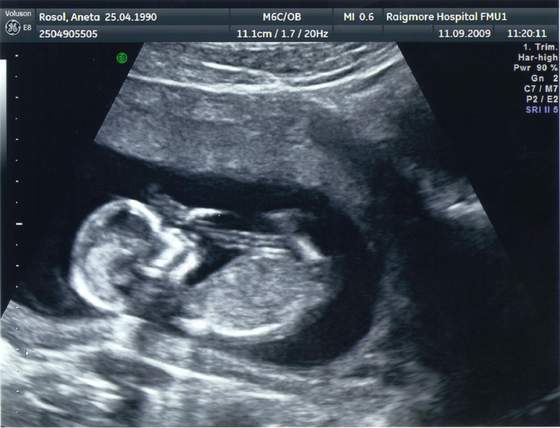

to moja kruszynka w 12 tygodzniu (troche spóźniałam się z wklejeniem)

śmieszne to zdjęcie, bo dzidziuś ma KOKA na głowieśmieje się, że to musi być dziewczynka